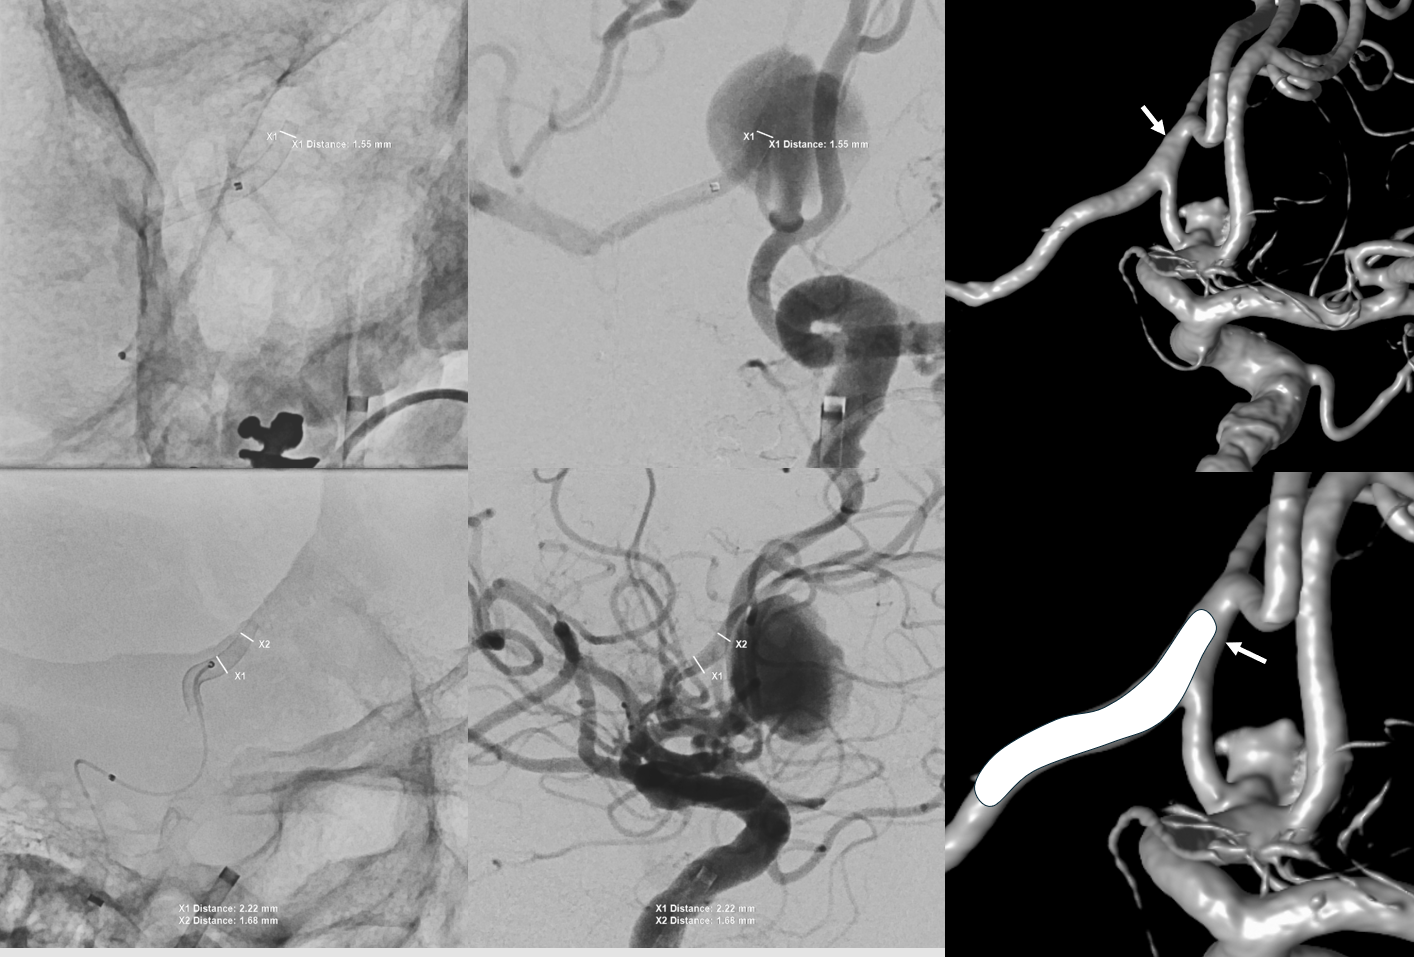

The first SVB is deployed. However, there is a concern. What is it? Look at the measurements of the SVB and the landing zones

The answer is possible endoleak. The distal landing zone may be too short for a nitinol device. The diameter of the proximal SVB is smaller than the expected diameter of the A2 target. Its a critical point. If this is missed, the treatment may fail

Look at the difference in measurements after SBV 2 (top row) and SBV 1 (bottom row). Arrows point to location of the SVB 1 distal landing zone

Now to the left side

Two Pipe Shields are placed. This is how we work. This big one is not a job for one and done

Post. Bilateral injections. The right ACA is supplied retrogradely via the ACA-ACA bypass. The MOST important finding here is that there is no longer flow across the ACOM. This is what flow modification is. Changing dynamics to impact aneurysm.